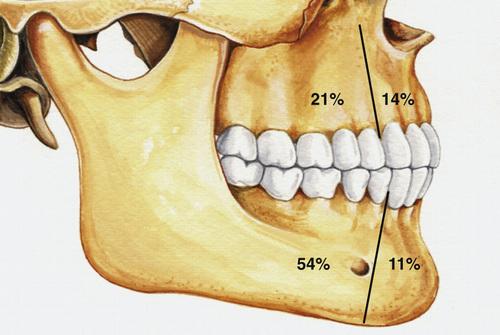

Radiographic Features

- unilocular radiolucent area

- associated with the crown of an unerupted tooth

- well-defined, often corticated border (unless infected)

- root resorption of adjacent erupted teeth can occur

- radiolucent space should be at least 3 to 4 mm in diameter